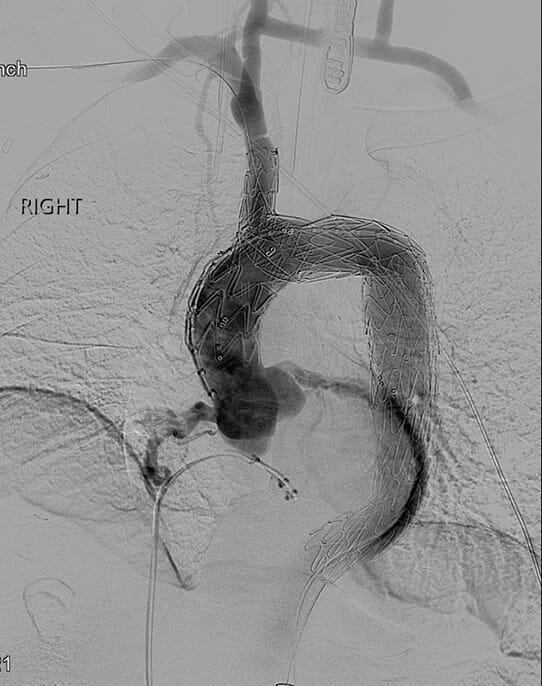

Aortic arch stent device in place shown on scanAortic arch stent device in place.

• Endovascular repair with Nexus aortic arch stent graft system - In stage one, the surgeon uses open techniques through a small incision in the neck to reroute cerebral and upper extremity blood flow by bypassing from the right carotid artery to the left carotid artery and the left subclavian artery. This technique avoids the need for open-chest surgery. Two to three days later, incisions in the groin enable deployment of the stent graft into the aortic arch and into the ascending aorta with a side branch graft into the innominate artery. Patients are typically able to return home a couple of days later.